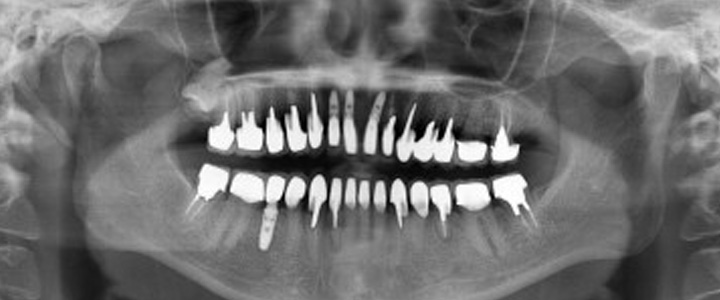

インプラント治療後の評価について、インプラント専門医の立場から治療の成功、あるいは問題について、どういった根拠て判断をするのか少しお話したいと思います。 …